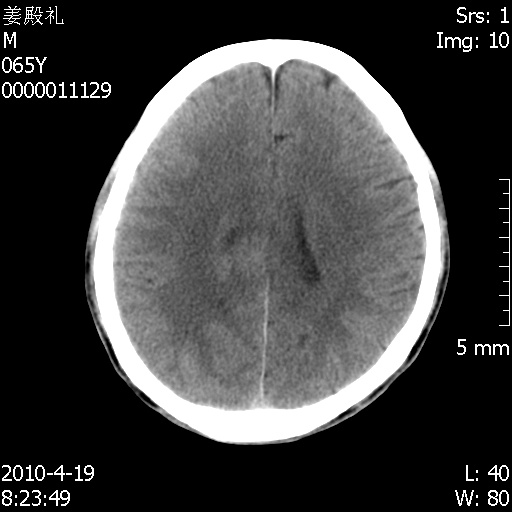

老年男性,突发左下肢无力1天,其余有价值的检查都没有。平扫ct值大约60hu,增强后ct值没什么改变,请大家讨论一下这个病例是什么?说明诊断理由。

今天上班后发现病人前天复查(4月18日发病,19日初诊,22日复查),三个病灶均明显增大,边缘仍旧清楚,水肿加重,右侧脑室基本闭塞。

今天遇到临床医生,询问病人情况,病人已经死亡。

最后看到的病人右侧瞳孔呈针尖大小,估计是继发脑干梗死,而非脑疝死亡。

遗憾! 复习了复查片:发现顶叶出血灶破入侧脑室,侧脑室体部见少许高密度。